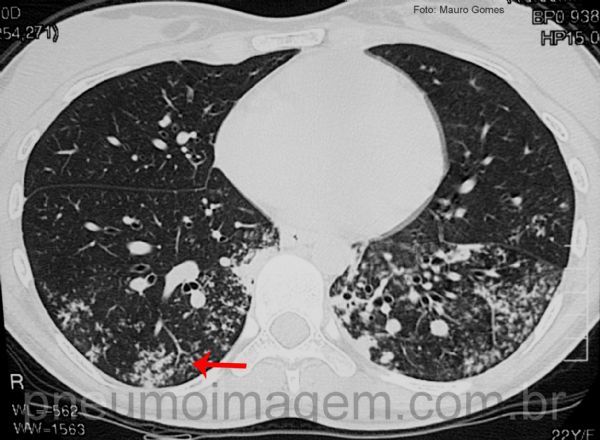

Tuberculose disseminada confirmada por cultura positiva para Mycobacterium tuberculosis.

Observe as lesões estendendo-se por ambos os pulmões. Incontáveis nódulos centrolobulares difusos, conferindo o aspecto de árvore em brotamento.

Disseminated tuberculosis confirmed by culture positive for Mycobacterium tuberculosis. Note the lesions extending over both lungs. Countless diffuse centrolobular nodules, giving the aspect of "tree in bud".

Nódulos centrolobulares difusos bilaterais conferindo o aspecto de árvore em brotamento. O sinal da árvore em brotamento caracteriza pequenas vias aéreas ou bronquíolos terminais preenchidos com muco, pus, fluidos ou células.

São opacidades nodulares ramificadas em V e Y que se assemelham a brotos de árvore. As opacidades se formam no centro do lóbulo pulmonar secundário e geralmente poupam a região subpleural, incluindo o espaço adjacente às fissuras.

Apesar de mais frequente em micobacterioses, pode ser sinal de várias infecções causadas por bactérias, fungos, parasitas e vírus.

Diffuse bilateral centrolobular nodules giving the appearance of budding tree. This signal features small airways or terminal bronchioles filled with mucus, pus, fluids, or cells.

They are nodular opacities branched into V and Y that resemble tree shoots. The opacities form at the center of the secondary pulmonary lobe and generally do not reach the subpleural region, including the space adjacent to the fissures.

Although more frequent in mycobacterioses, it can be a sign of several infections caused by bacteria, fungi, parasites and viruses.